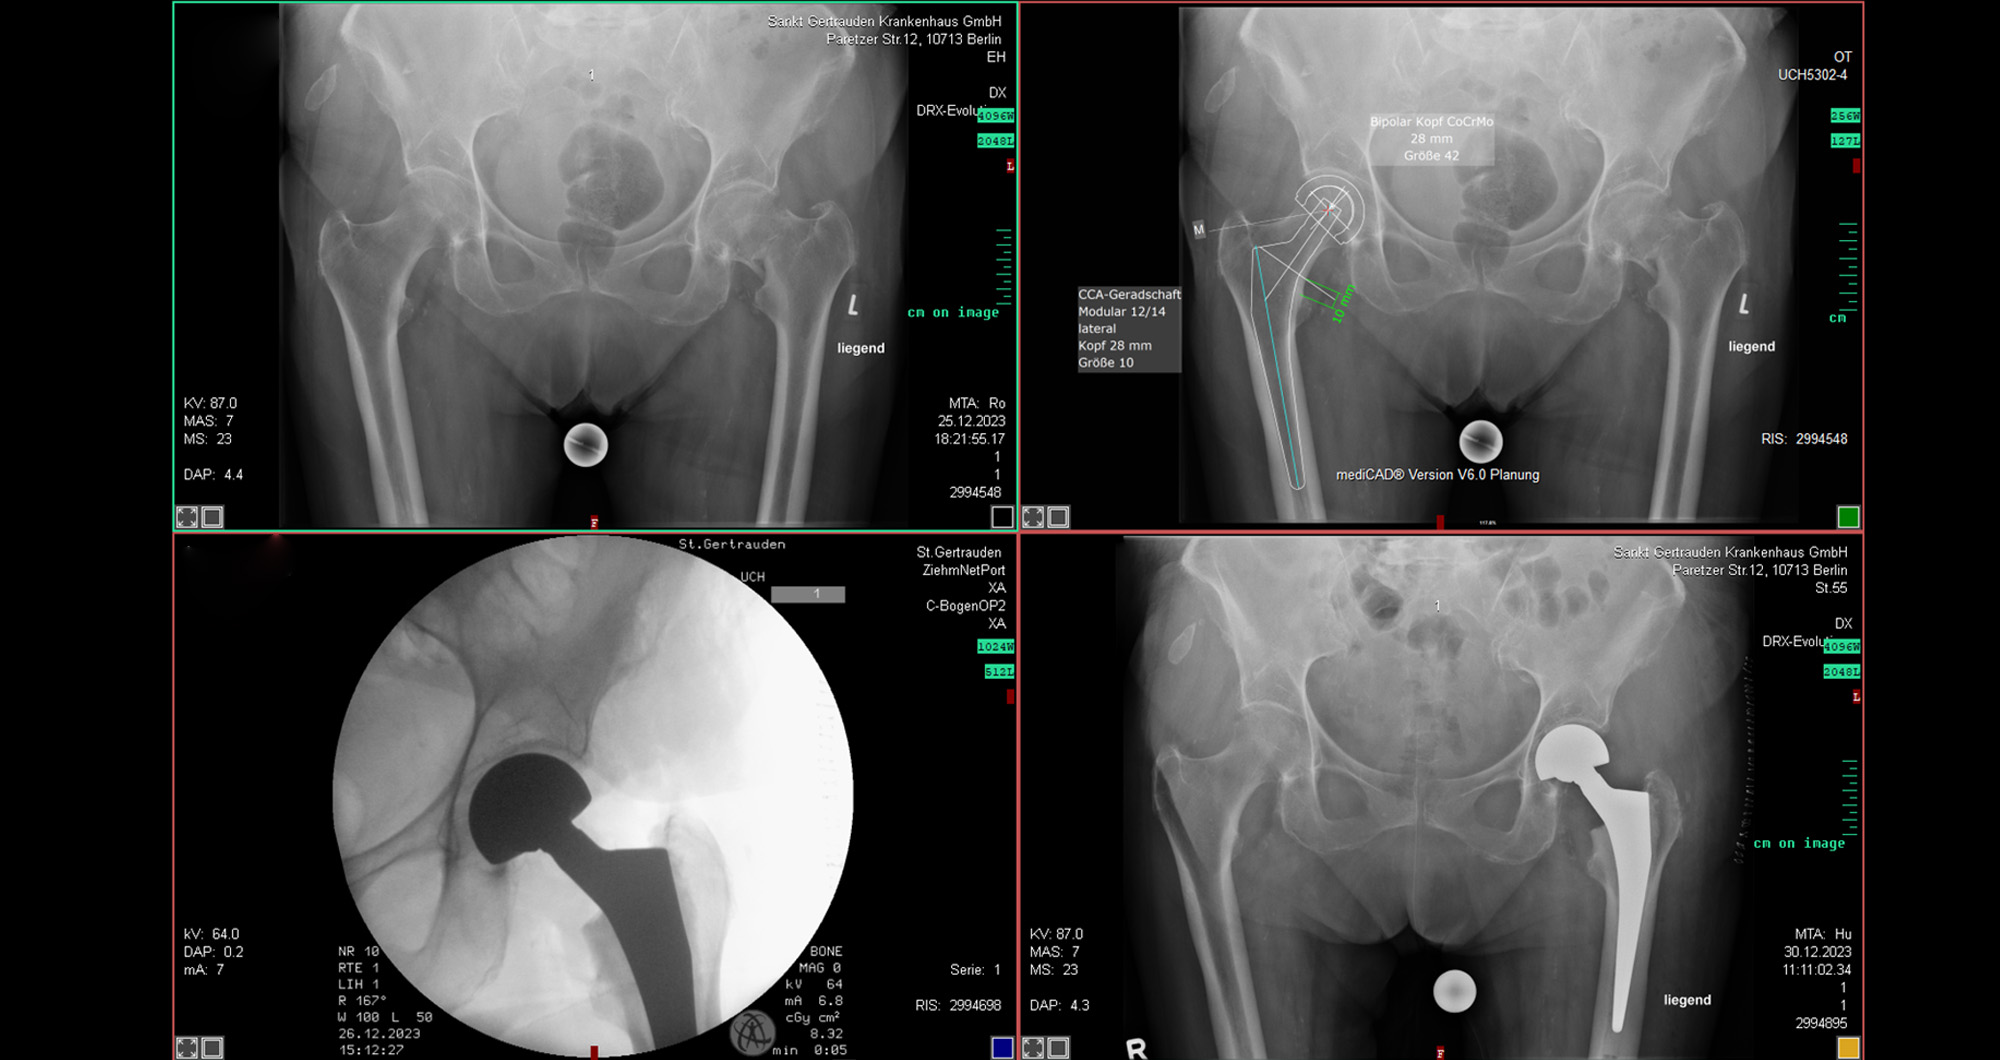

Von links oben in Uhrzeigerrichtung: 1.Mediale Schenkelhalsfraktur mittels Duokopfprothese 2. Mediale Schenkelhalsfraktur mittels Hüft-TEP in Hybrid-Technik (teilzementiert) 3. Mediale Schenkelhalsfraktur mit DHS inkl. Antirotationsschraube 4. Mediale Schenkelhalsfraktur mit Hüft-TEP zementiert 5. Laterale Schenkelhalsfraktur/pertrochantäre Femurfraktur mit Hüft-TEP durch Rekonstruktionsschaft zementfrei 6. Subtrochantäre Fraktur mit TFNA Lang inkl. Cerclage 7. Mediale Schenkelhalsfraktur mit einem kurzen Nagel bei pertrochantärer Fraktur